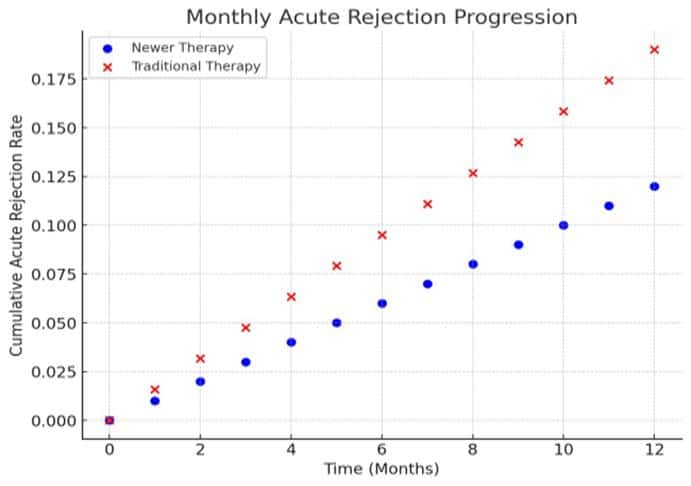

Urology | Oct 22, 2024

Innovations in Immunosuppressive Therapy and Their Impact on Kidney Transplants in the UK: A Descriptive Analysis

Background: Kidney transplantation is the optimal treatment for end-stage renal disease (ESRD), significantly improving patient survival and quality of life...Read More